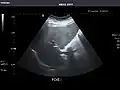

Abdominal Ultrasound (Full Exam)

STRUCTURED REPORT

(Technique: Transabdominal ultrasonography; Device: Toshiba Aplio XG)

Liver: Diffusely homogeneous and normal in echogenicity. No focal mass or contour nodularity. No intrahepatic biliary ductal dilatation.

Portal Vein: Patent main portal vein.

Gallbladder: No stones, wall thickening, or pericholecystic fluid.

Common Bile Duct: Nondilated measuring 1.3 mm at the level of the porta hepatis.

Pancreas: Visualized portions unremarkable.

Spleen: Normal in size.

Kidneys: Right and left kidneys measure 11.5 cm and 12 cm in length respectively. No hydronephrosis. Small left lower pole kidney cyst.

Ascites: None.

Aorta: Visualized portions normal in caliber, 16 x 15 mm.

IVC: Normal.

IMPRESSION:

Normal abdominal ultrasound.